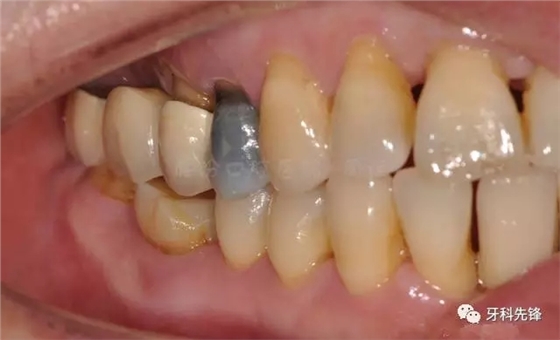

圖2 術(shù)前側(cè)位咬頜照

640.webp (3).jpg